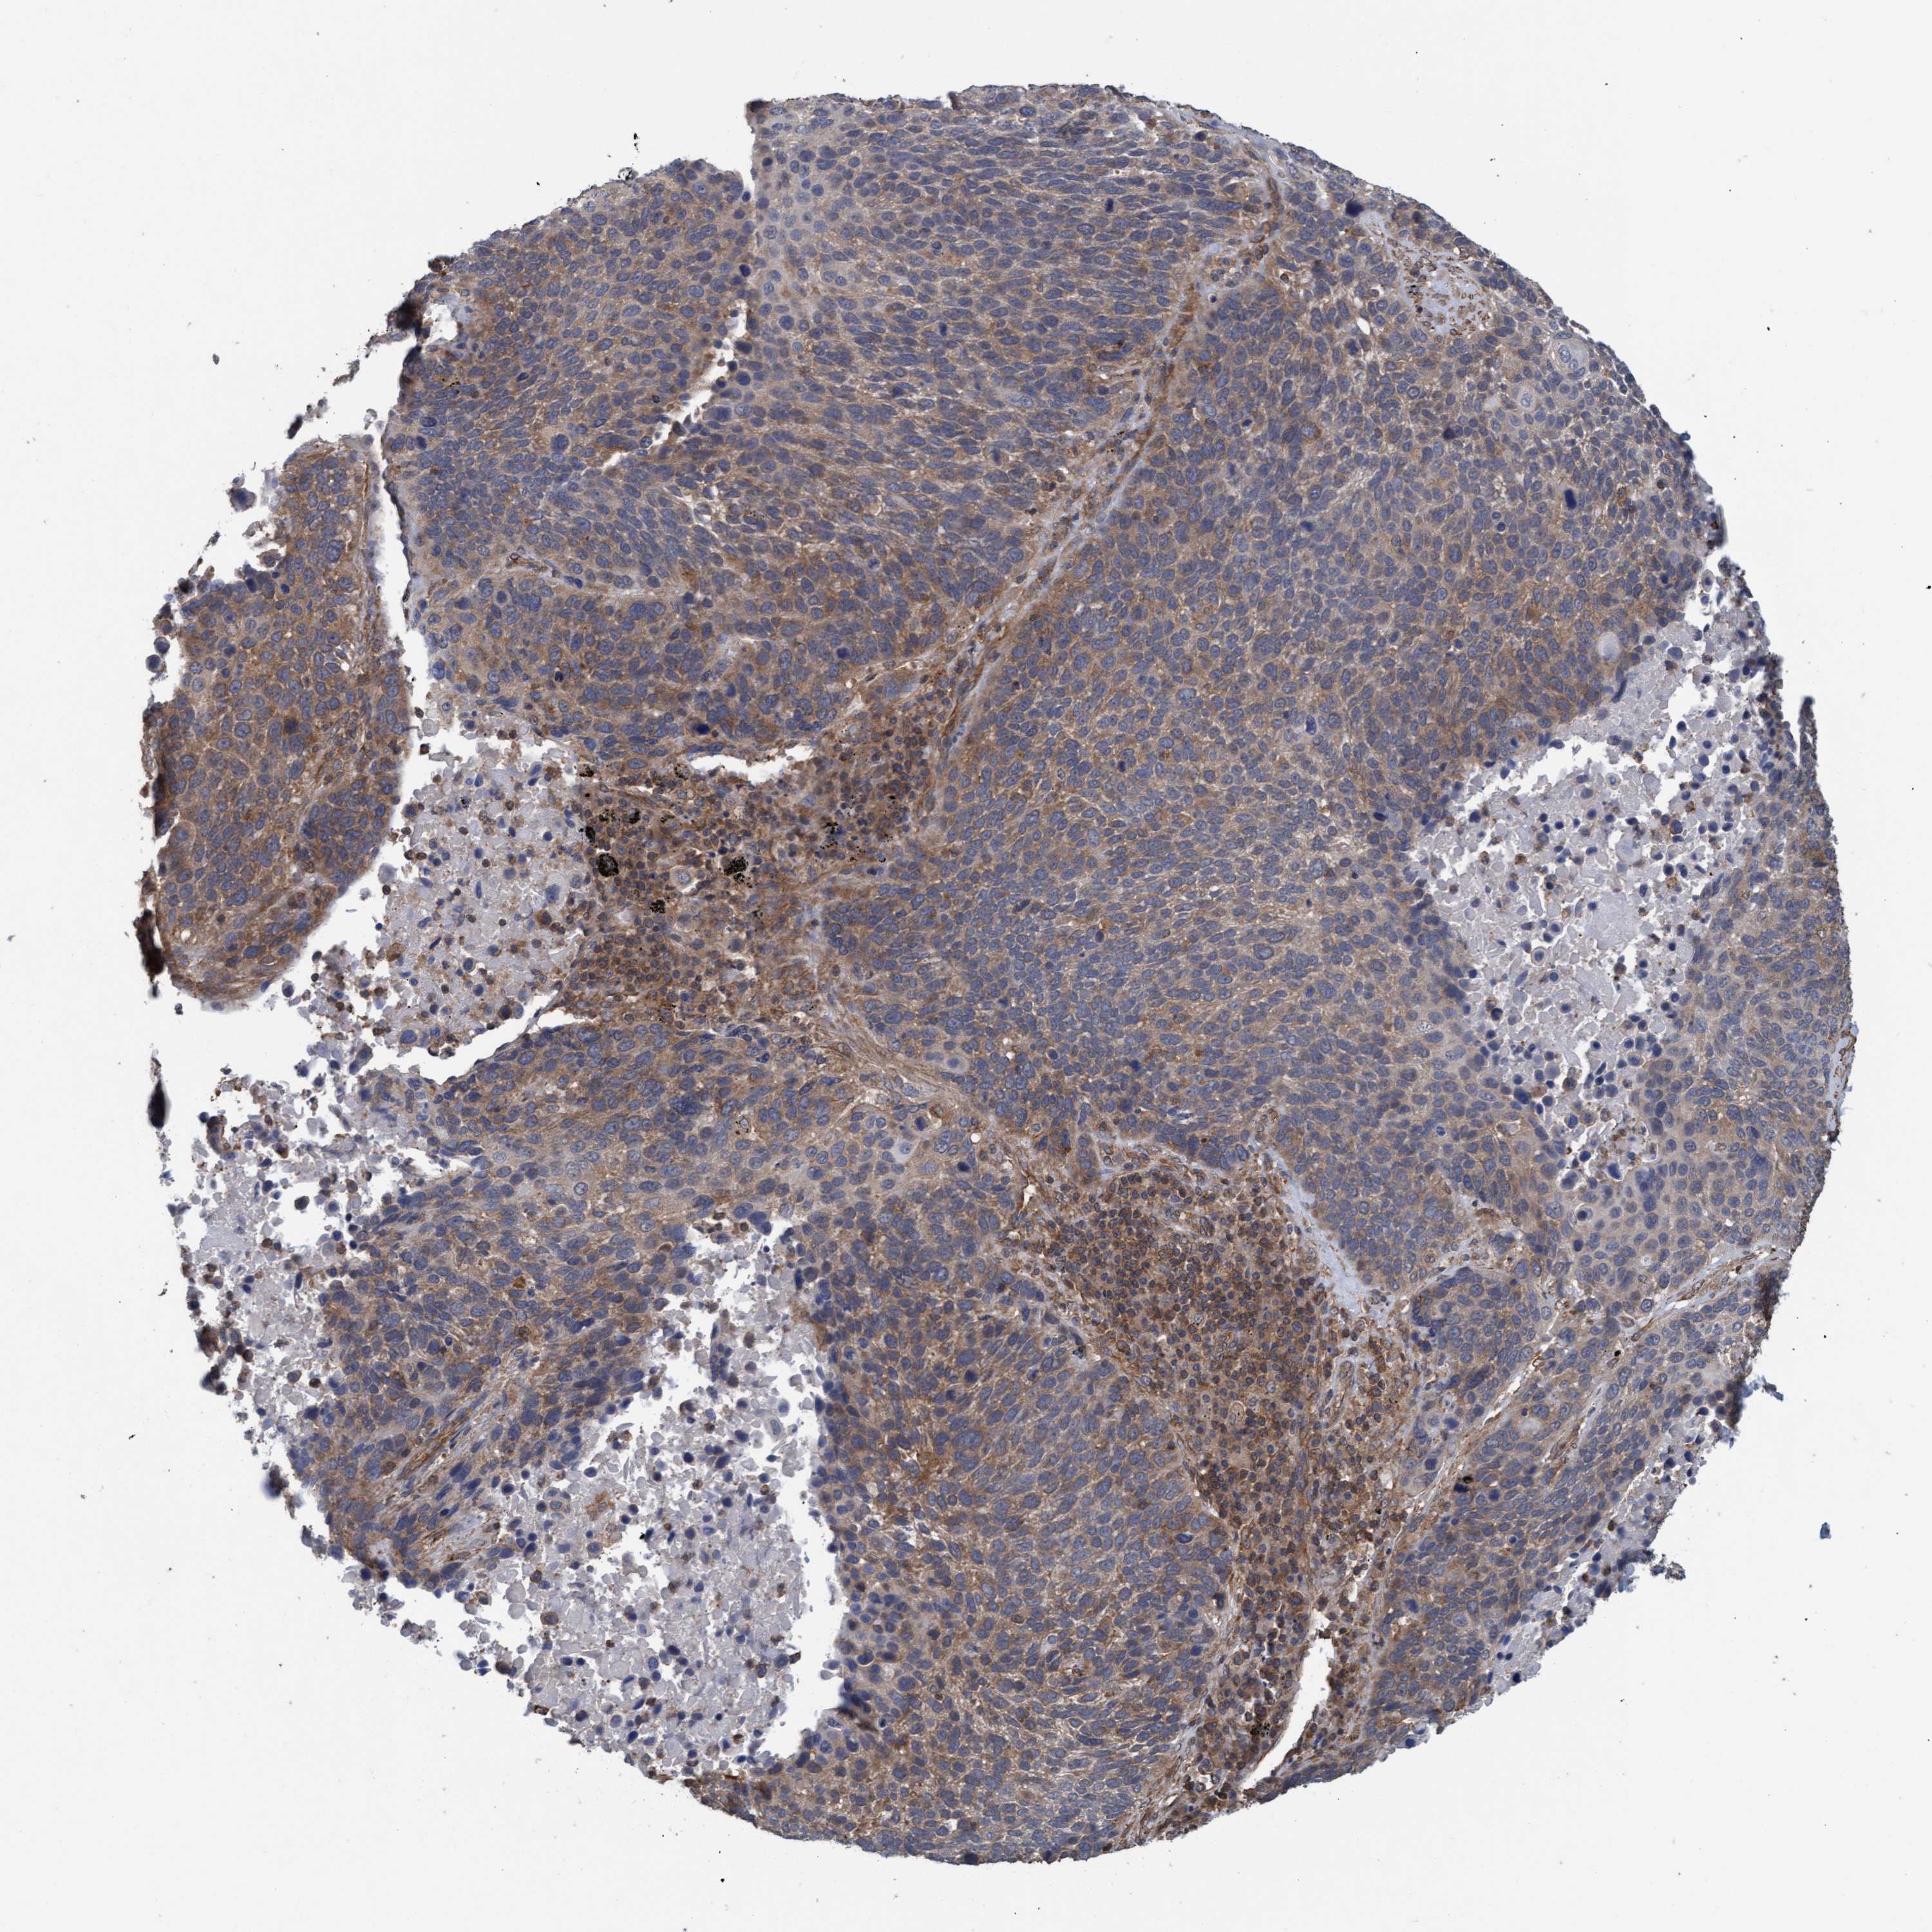

LUNG SQUAMOUS CELL CARCINOMA (TCGA) - Interactive survival scatter ploti

The Survival Scatter plot shows the clinical status (i.e. dead or alive) for all individuals in the patient cohort, based on the same data that underlies the corresponding Kaplan-Meier plots. Patients that are alive at last time for follow-up are shown in blue and patients who have died during the study are shown in red.

The x-axis shows the expression levels (FPKM) of the investigated gene in the tumor tissue at the time of diagnosis. The y-axis shows the follow-up time after diagnosis (years). Both axes are complimented with kernel density curves demonstrating the data density over the axes. The top density plot shows the expression levels (FPKM) distribution among dead (red) and alive patients (blue). The right density plot shows the data density of the survived years of dead patients with high and low expression levels respectively, stratified using the cutoff indicated by the vertical dashed line through the Survival Scatter plot. This cutoff is automatically defined based on the FPKM cutoff that minimizes the p-score. The cutoff can be changed by dragging the vertical line or by entering a cutoff value in the square labeled "Current cut-off".

Under the Survival Scatter plot the p-score landscape (black curve; left axis) is shown together with dead median separation (red curve; right axis). Dead median separation is the difference in median mRNA expression between patients who have died with high and low expression, respectively. It is calculated as follows: median FPKM expression of dead patients with high expression - median FPKM expression of dead patients with low expression. This is intended to aid the user in visually exploring custom cutoffs and the associated p-scores and dead median separation.

Individual patient data is displayed and can be filtered by clicking on one or more of the category buttons on the top of the page. Categories describing expression level and patient information include: high, low, alive, dead, female, male and tumor stages. The scale of the x-axis can be toggled between linear and log-scale by clicking on the "x log" button. Mouse-over function shows TCGA ID, patient information and mRNA expression (FPKM) for each patient.

& Survival analysisi

Kaplan-Meier plots summarize results from analysis of correlation between mRNA expression level and patient survival. Patients were divided based on level of expression into one of the two groups "low" (under cut off) or "high" (over cut off). X-axis shows time for survival (years) and y-axis shows the probability of survival, where 1.0 corresponds to 100 percent.

FXR2 is not prognostic in Lung Squamous Cell Carcinoma (TCGA)

Best expression cut offi

: 23.48

P scorei

N/A

TCGA RNA samplesi

RNA-seq data is reported as average FPKM (number Fragments Per Kilobase of exon per Million reads), generated by the The Cancer Genome Atlas (TCGA) .

Normal distribution across the dataset is visualized with box plots, shown as median and 25th and 75th percentiles. Points are displayed as outliers if they are above or below 1.5 times the interquartile range. FPKM values of the individual samples are presented next to the box plot.

Average pTPM 19.4

Number of samples 489